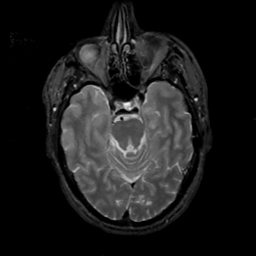

MR Study #6, March 17, 1991 -- Slice #17

[Home][Help][Clinical][Tour 1][Tour 2] Slice 17